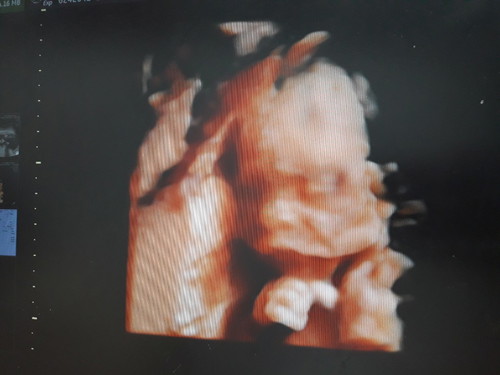

มาโชว์รูปซาวกันจ้าได้ ช หรือ ญ กันจ้า

บ้านนี้ซาวตอน21วิค ได้ลูกชายจ้า

ซาวด์เมื่อวันพุธ ตอนนี้ได้ 32+2w ลูกชายค่ะ จะถ่ายในจอแต่หมอไม่ให้ถ่าย หมอปริ้นท์แบบนี้มาให้ 😆

ซาวด์ตอน 22วีค ได้ผู้หญิงจ้า ปัจจุบัน 24+4วีคจ้า

ตอน30วีคค่ะ แอบยิ้มด้วย ผช.